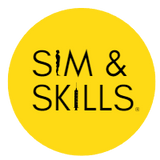

This 3D print provides a detailed view of head and neck anatomy, showing different structures depending on the perspective.

Brain and Cranial Cavity

The medial cerebrum shows the corpus callosum, thalamus, sulci, and gyri, while parts of the cerebellum are removed to expose the cranial fossae floor and fourth ventricle. The cavernous sinus, sella turcica, and intracranial course of cranial nerves II, III, V, VII–X, XI are displayed, including the facial canal and geniculate ganglion.

Medial Surface and Key Vessels

The parasagittal section reveals the lateral ventricle, cerebral peduncle, posterior cerebral artery, and the tentorium cerebelli. The internal carotid artery in the cavernous sinus is shown lateral to the optic chiasm. Additional structures include the mouth, tongue, associated muscles, nasal cavity, nasopharynx, and cervical vertebrae.